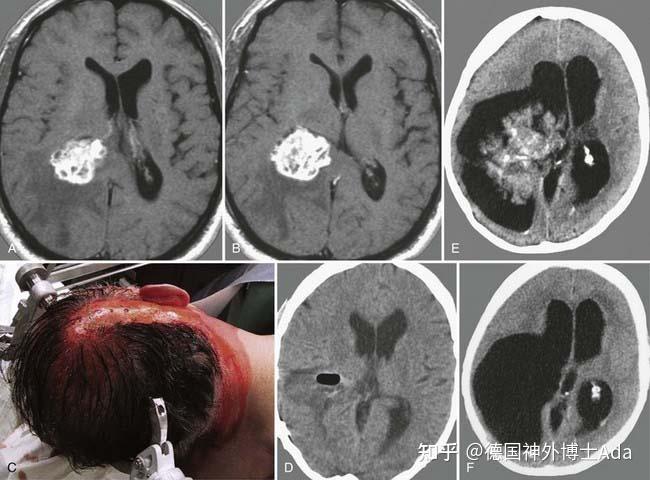

脉络丛癌.

注意肿瘤浸润和周围脑组织肿胀必,更符合脉络丛癌的特点,导致中线移位